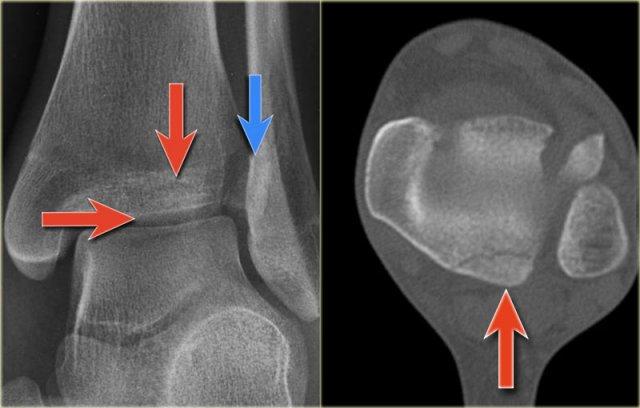

Các hình ảnh cho thấy một trường hợp gãy Weber B rõ ràng.

Trên tư thế thẳng (AP), đường thấu quang dạng tuyến tính là dấu hiệu gợi ý gãy tertius (mũi tên đỏ).

Dấu hiệu này xuất hiện do sự lệch trục nhẹ của mảnh gãy.

Tương tự, trong một số trường hợp, sự lệch trục có thể tạo ra một đường tăng tỷ trọng dạng tuyến tính.

Trong trường hợp này, có gãy Weber B kèm theo bong điểm bám mắt cá trong.

Đường tăng tỷ trọng trên tư thế thẳng (AP) gợi ý một mảnh gãy tertius lớn.

Gãy tertius này cũng có thể thấy trên tư thế nghiêng, nhưng trong nhiều trường hợp chúng ta cần kết hợp thông tin từ cả hai tư thế nghiêng và thẳng để chẩn đoán gãy tertius.